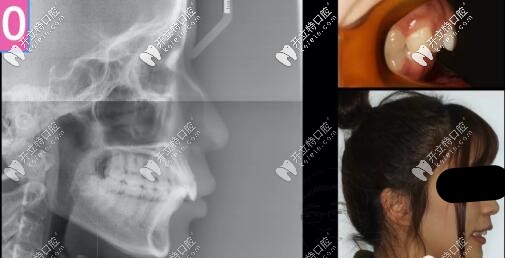

26歲女孩,來診主訴:嘴凸,大笑露牙齦,強烈訴求是解決嘴凸問題。

二類骨性齙牙正畸案例

側(cè)貌微凸,深覆合

右側(cè)磨牙尖牙關(guān)系II類,左側(cè)I類,

深覆合覆蓋5mm,下頜牙弓擁擠度5mm

骨性二類凸嘴拔牙內(nèi)收案例

側(cè)位片提示:

骨性II類,均角,上前牙舌傾,下前牙唇傾前凸